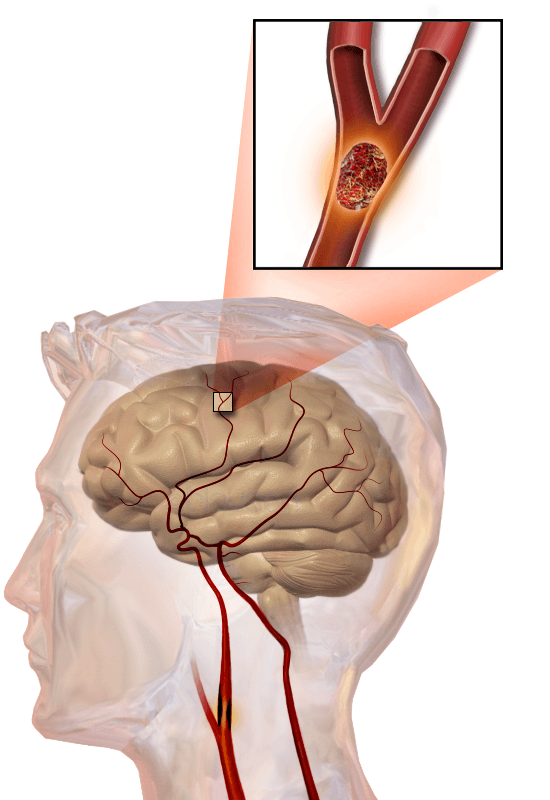

Ischemic Stroke

- “Clogged pipes” are known as ischemic strokes. Ischemic stroke happens when a blood vessel in the brain is blocked, preventing blood flow to the brain. When this happens, a portion of the brain is at risk. Ischemic strokes, or “clogged pipes,” are the most common type of stroke, attributing to 80% of all stroke cases.

What treatment is available for ischemic stroke?

Treatment for ischemic stroke is very effective and available, but it is also time-dependent. It is very important to act quickly if you or a loved one is experiencing stroke symptoms.

When you have an ischemic stroke, you lose brain cells at a staggering rate. It is estimated that two-million brain cells are lost per minute during an ischemic stroke. However, there are two highly effective therapies for ischemic stroke. One treatment for ischemic stroke isTenecteplase, a clot-busting medication that is administered by experts after it is determined that you are having an ischemic stroke.

Another treatment for ischemic stroke is a thrombectomy, which is a procedure for large blockages in the blood vessels of the brain. During a thrombectomy, experts navigate a catheter into the brain to locate the blood clot and pull it out.